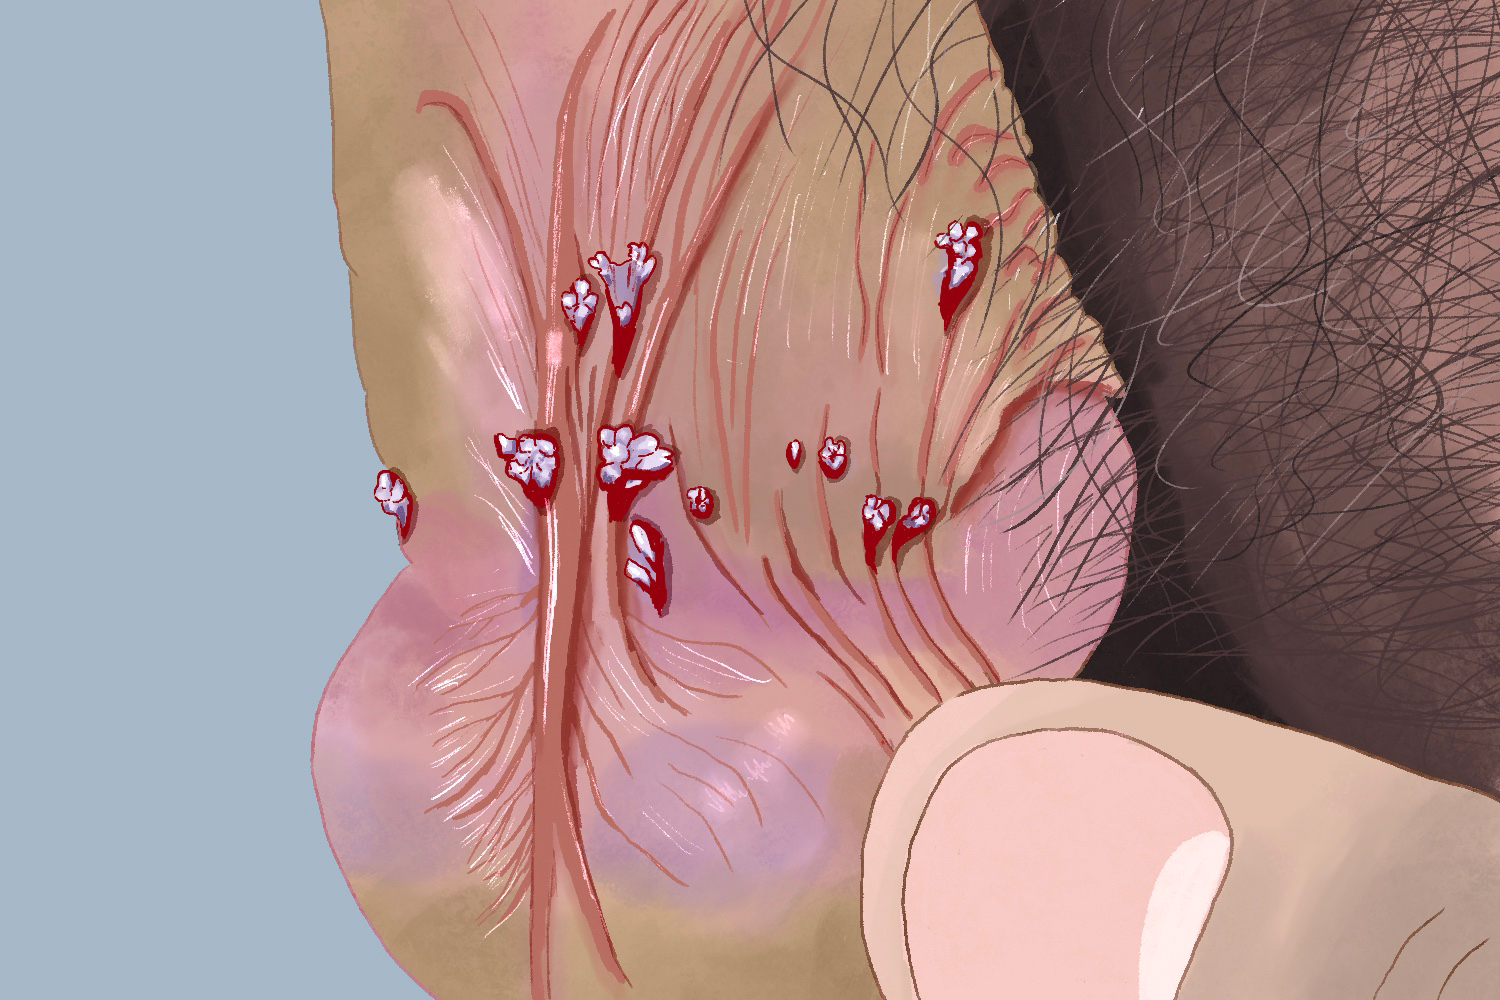

尖锐湿疣的皮损初期表现为局部细小丘疹,针头至粟粒大小,逐渐增大或增多,向周围扩散、蔓延,渐发展为乳头状、鸡冠状、菜花状或团块状赘生物。损害可单发或多发,色泽可从粉红至深红、灰白乃至棕黑。皮损多发生在生殖器及周围皮肤上,另外也可发生于肛周和口腔。